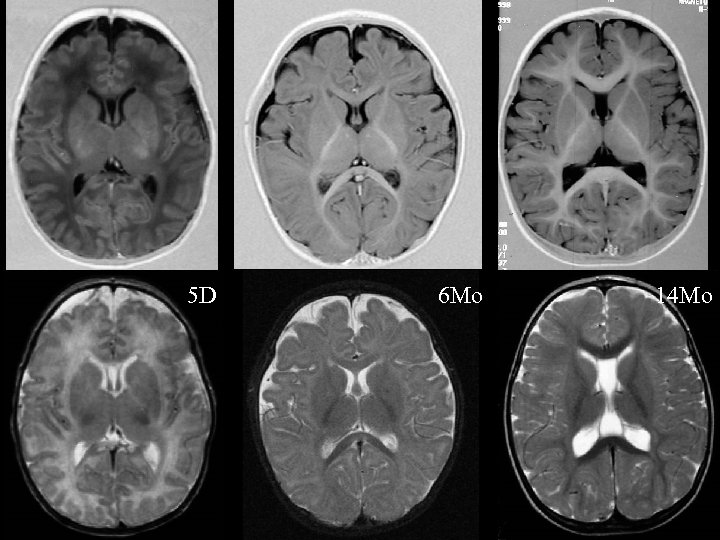

5 D 6 Mo 14 Mo 5 D 6 Mo 14 Mo